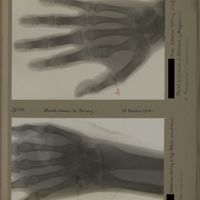

0177 - Page 65 - [Radiographie de la main gauche] / [Radiographie de la main droite]0177 - Page 65 - [Radiographie de la main gauche] / [Radiographie de la main droite]